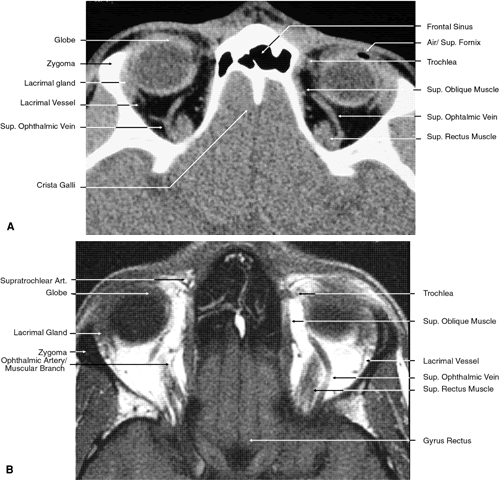

The globe is shown in Figure 12. The orbit and periorbital structures are shown in Figures 13 through 16, and the optic canal is shown in Figures 17 through 26. The cavernous sinus and optic chiasm are shown in Figures 27 and 28, and the posterior visual pathway and cranial nerves are shown in Figures 29 through 33.

Fig. 19. Coronal images through midorbit posterior to the globe. A. Computed tomography scan.B. T1-weighted magnetic resonance imaging.

Fig. 20. Coronal images through orbital apex. A. Computed tomography scan. B. T1-weighted magnetic resonance imaging. C. Anatomic section of a cadaver head at the level of the orbital apex.

The orbital roof is approximately triangular and is composed of the frontal bone anteriorly and the lesser wing of the sphenoid posteriorly. The roof is markedly concave, with the greatest degree of this concavity in the area of the equator of the globe (see Fig. 26). At the anterior and lateral portion of the orbital roof lies the lacrimal gland in the lacrimal fossa (see Figs. 18 and 23). This gland consists of a large orbital portion and a smaller palpebral portion. The orbital portion normally measures 20 × 12 × 5 mm, whereas the palpebral portion is about one third of this size.49 The supraorbital notch is at the junction of the nasal third and the lateral two thirds of the bony orbital margin (see Fig. 1). The trochlea of the superior oblique muscle is located 4 mm posterior to the orbital margin in the medial and anterior portion of the orbital roof (see Figs. 17, 24, and 25). Although usually a cartilaginous structure, it is occasionally partially or wholly ossified. It measures 4 × 6 mm and is firmly attached by connective tissue to the periosteum. The frontal bone portion of the orbital roof is extremely thin and like the orbital floor is subject to so-called blow-in fractures as well as to penetrating injury.50 The posterior portion of the roof is more substantial, measuring 3 mm thick. Except for the anterior portion of the orbit, the intracranial cavity lies directly superior to the orbital cavity (see Fig. 26). The levator muscle and the superior rectus muscle just inferior to it are present along the midportion of the orbital roof for all but its most anterior portion (see Fig. 26). The superior oblique muscle, after it changes direction at the trochlea, is present inferior to the anterior portion of the roof and inserts onto the globe inferior to the superior rectus muscle.

The orbital floor is similar in shape to the triangular orbital roof and is composed of the maxillary, zygomatic, and palatine bones. Medially, the bony lacrimal canal containing the nasolacrimal duct lies just posterior to the inferior orbital rim (see Fig. 22). At this point the canal is formed by the maxillary and lacrimal bones. Just lateral to the bony canal is the origin of the inferior oblique muscle. Laterally, the floor is separated from the lateral orbital wall by the inferior orbital fissure, which begins lateral and inferior to the optic foremen and near the inferior aspect of the superior orbital fissure. It is approximately 20 mm long, ending 20 mm posterior to the lateral portion of the inferior orbital margin (see Fig. 14). The boundaries of the fissure are the maxillary and palatine bones medially, the greater wing of the sphenoid bone posteriorly, and the zygomatic bone laterally and anteriorly. Inferior to the orbital floor over most of its area is the maxillary sinus (see Figs. 5, 19, and 26). The bone of the floor is 0.5 to 1.0 mm thick, being thinnest at the inferior orbital groove and canal. The fragility of this bone is the reason it is commonly fractured during orbital trauma and the reason for orbital extension of sinus tumors. The ethmoid air cells are occasionally found within the orbital floor medially, and posteriorly there may be a sinus within the orbital portion of the palatine bone.48 The medial rectus muscle runs along the middle aspect of the floor until it inserts into the globe. It is in contact with the floor posteriorly, but anteriorly it is superior to the inferior oblique muscle (see Fig. 19).

The full extent of the orbital roof and floor as well as the superior and inferior rectus muscles and the levator muscle is best evaluated using sagittal views of the orbit (see Figs. 17 through 20, 26). Reconstructed images are generally too crude to provide detailed imaging of these structures. Coronal views of the orbit are excellent for showing the vertical dimension of the lateral and medial orbital walls and the horizontal dimension of the orbital roof and floor. This view is also important for showing the cross-sectional areas of the globe and orbital soft tissue structures, including the muscles, nerves, vessels, and orbital fat.